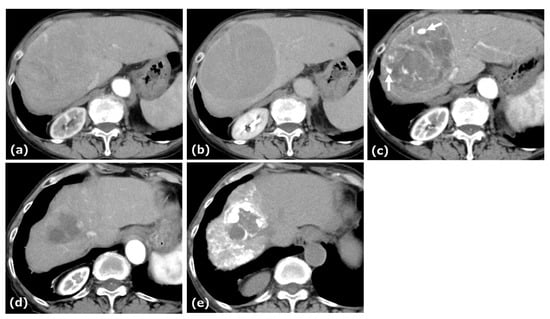

A woman in her eighties was referred to our hospital for evaluation of a hepatic mass, incidentally detected on ultrasonography during a workup for abnormal liver enzymes. Her medical history included hypertension and dyslipidemia. Laboratory data and tumor markers were as follows: AST: 54 U/L, ALT: 50 U/L, LDH: 185 U/L, ALP: 138 U/L, γ-GTP: 48 U/L, total bilirubin: 1.2 mg/dL, AFP: <0.9 ng/mL, PIVKA-II: 9795 mAU/mL, CEA: 4.2 ng/mL. Anti-HBs was 18.3 mIU/mL, whereas anti-HBc was 0.1 S/CO. The Child–Pugh score was 6. CE-CT revealed an approximately 14.5 cm tumor in segment 8 of the liver, showing arterial-phase enhancement with central necrosis, a pseudocapsule, and an intratumoral artery, followed by washout in the portal and delayed phases (Figure 2).

Figure 2. CE-CT of Case 2. CE-CT in the arterial and portal phases showed a large hypervascular HCC with central necrosis and a pseudocapsule in the anterior segment of the liver (a,b). After five cycles of AB therapy, arterial-phase CT demonstrated a vascular lake-like phenomenon ((c), arrow). On arterial-phase CT obtained after a total of seven cycles of AB therapy, tumor regression was observed (d).

The tumor extended into the middle hepatic vein, forming a venous thrombus. AB therapy was initiated as the first-line treatment for this patient. After five cycles of this combination therapy, tumor size decreased from 14.5 cm to 7.0 cm, and treatment response was categorized as a PR according to RECIST 1.1. At this time, patchy pooling of contrast medium within the tumor was also observed. After seven cycles of this therapy, the response was categorized as a PR based on RECIST 1.1, and conversion therapy was planned.